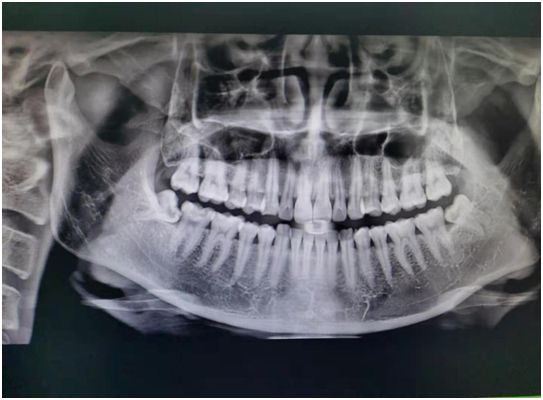

全景片就是可以在一张胶片上可以完整、清晰地显示上颌骨、下颌骨全貌,上下颌牙列情况,牙槽骨情况,能清晰显示上颌窦腔、窦壁、窦底情况,以及颞颌关节情况,并对颌骨周围疾病的诊断提供帮助。

拍摄全景片是口腔治疗之前很重要的一个检查过程,医生通过全景片可以观察到牙齿的健康状况,是否有隐形龋齿、埋伏阻生牙、多生牙、牙槽骨吸收、牙龈萎缩、口腔内是否长有瘤体等。

在做牙齿种植、牙齿矫正、牙齿修复、智齿拔除等之前,均需要拍摄口腔全景片。

1. 牙齿的解剖结构、密度,牙周状况的检查。

2.埋藏牙定位及周边相邻关系判断。

3.牙齿发育情况判断。

4.牙齿矫正前的病例分析、测量,指导矫正方案的制定。

5.种植前牙槽骨的质、量的评价及种植体大小、长短的确定。

6.牙列缺失复杂修复前基牙的评估。

7.头面部外伤,骨折的诊断。

8.根管充填、镶牙、种植、矫正效果的复查、评估。

9.智齿拔除等外科手术方案制定和风险评估。

10.头、面部肿瘤、囊肿的筛查,鉴别。